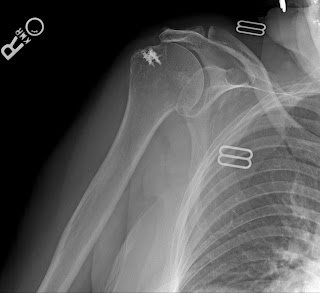

The x-rays below are from a different patient but the operation was by the same surgeon. In this patient, there is moderate pain because the anchors remain in the bone. The repair has failed. If you look carefully, you can see that the head of the humerus (the bone with the metal anchors) has moved upwards and now is touching the bone above it (the acromion). This can only happen when there is a massive rotator cuff tear. Once again, no MRI needed. This patient cannot lift her arm at all and has what we call a pseudoparalyitc shoulder.

This patient is considering a reverse should arthroplasy. She is the same age as the first patient but much more active. I suspect she would do well with the new shoulder.